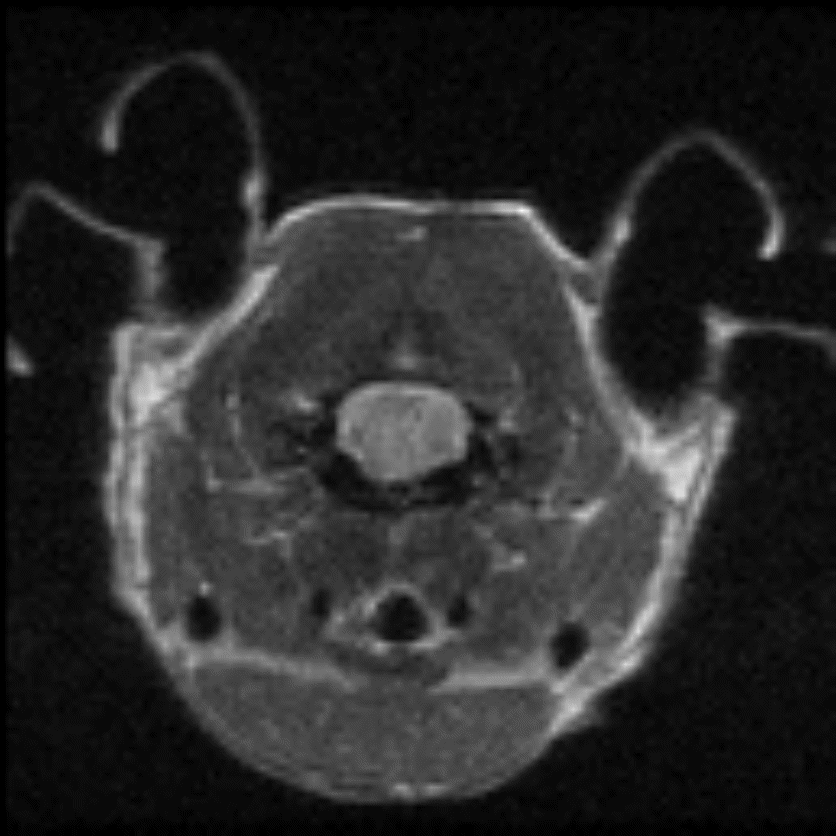

Tumor visualization in various cancer models: Fat-suppressed T2-weighted imaging can be used to detect and quantitatively characterize the growth of a wide range of cancer models. Image Credit: Scintica Instrumentation Inc

Fat-suppressed T2-weighted imaging can be used to detect and quantitatively characterize the growth of a wide range of cancer models. Image Credit: Scintica Instrumentation Inc